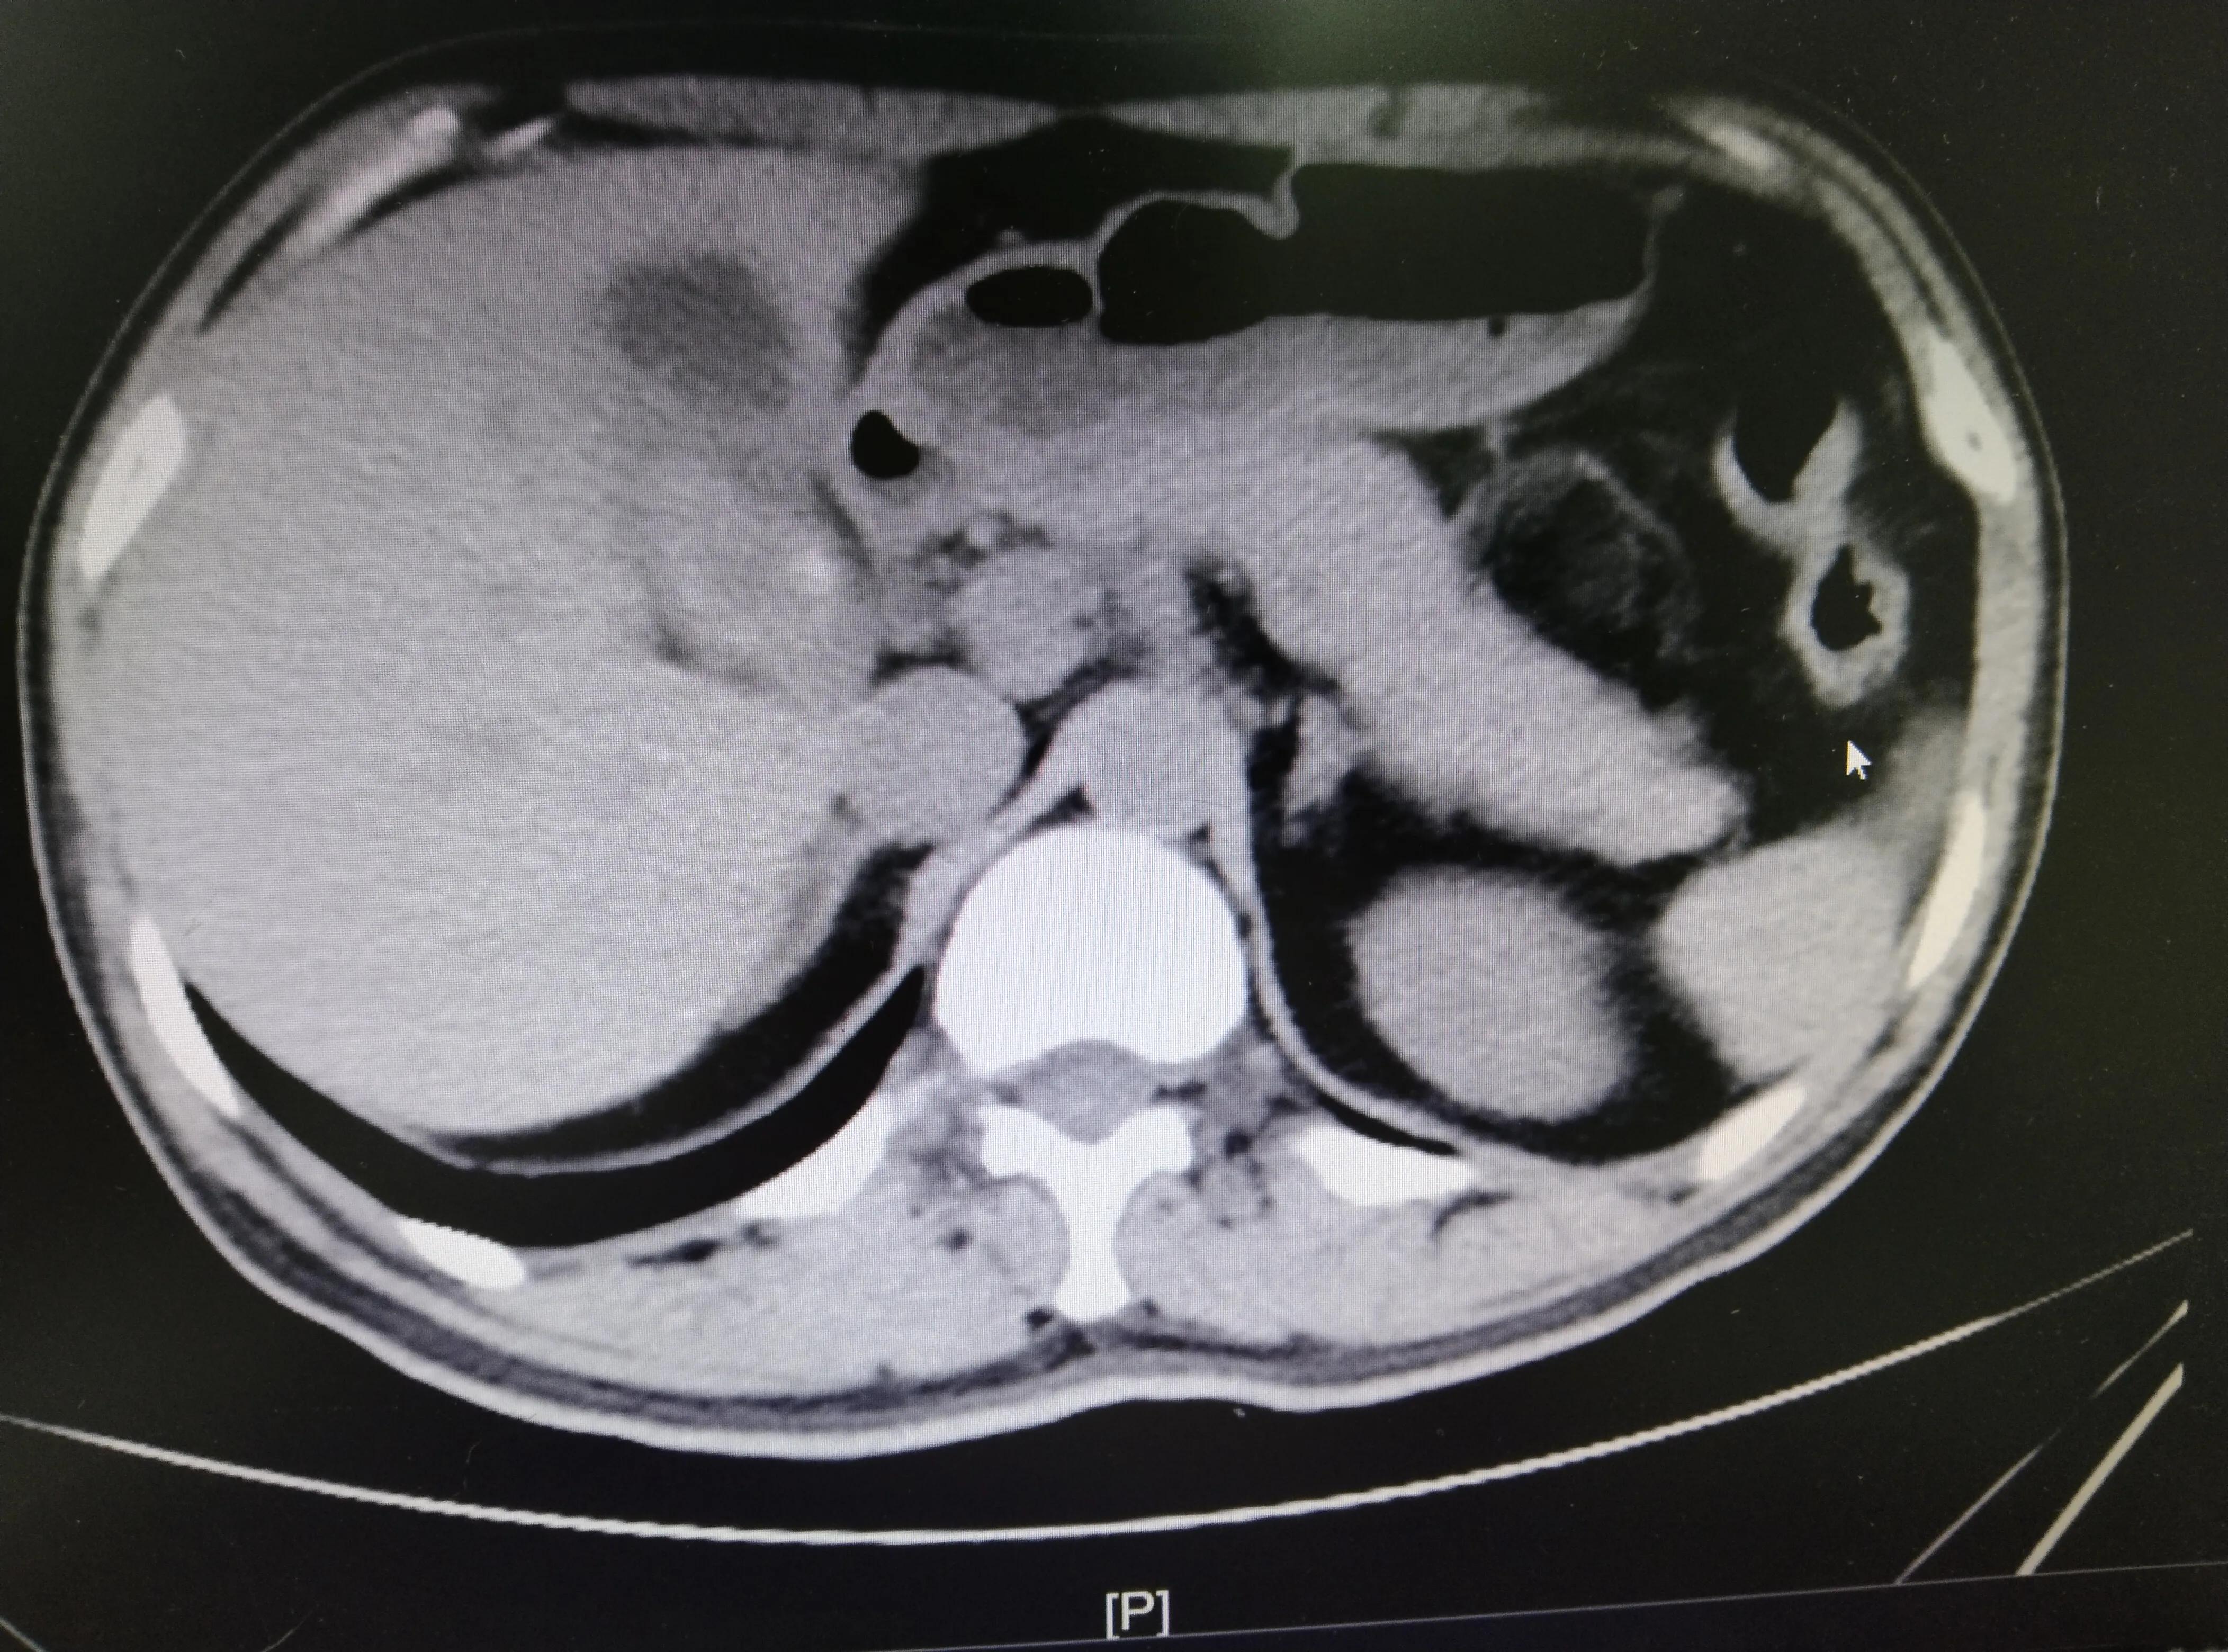

一位三十岁的年轻帅小伙小张,是一名司机,平常忙于生计,发现胆结石多年,反复腹痛一直强忍。年前一次聚会导致胆源性胰腺炎,腹痛难忍,高热不退才来住院,经抗感染治疗后才同意手术治疗。术中可见胆囊内两个4*3厘米“田螺”状结石,长期的炎症形成肝脓肿,引流出大量坏死肝组织及脓液,胆囊壁厚达1厘米,不排除恶变的可能性。由此可见,小张未听从医生的建议,错过最佳手术时机,不仅增加了手术的风险和难度,还给自己带来更多严重的后果。为此,小张也十分懊悔。

胆结石不治疗的后果我们已经知晓,那么胆结石该如何诊断和治疗呢?对疑有胆囊结石的患者可首选B超检查,无创且操作简单,CT对胆囊结石的诊断也有很高的敏感度和特异性。根据《胆囊良性疾病专家共识2021版》手术指征:(1)胆囊结石,无论是否有症状;(2)有相关并发症,如继发性胆总管结石、胆管炎、胆源性胰腺炎等;(3)具有胆囊癌危险因素,如胆囊萎缩、充满型结石、瓷化胆囊、胆囊壁增厚(≥3 mm)、胆囊肿瘤性息肉等;(4)合并先天性胰胆管汇合异常、原发性硬化性胆管炎、肥胖与糖尿病等;(5)胆囊畸形等。符合上述任何一项者,都应择期行腹腔镜胆囊切除术。